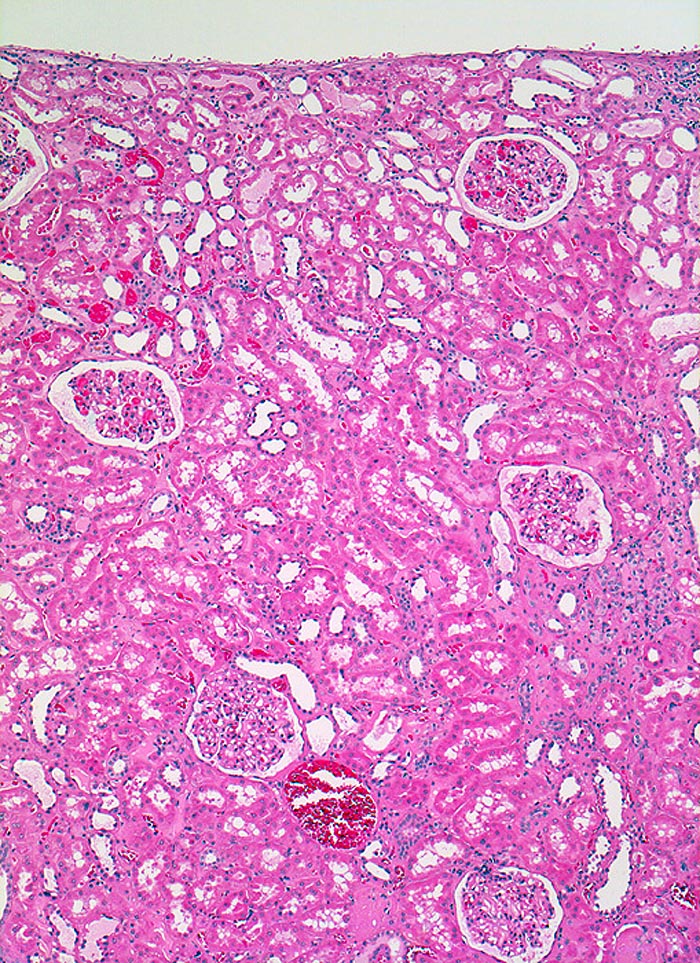

Normale Nierenrinde

Normalbefund

Niere

Unauffällige Nierenrinde

Histologie

50

64

männlich